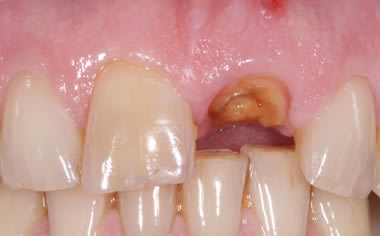

More front teeth replaced by dental implants

Case Three (4 images)